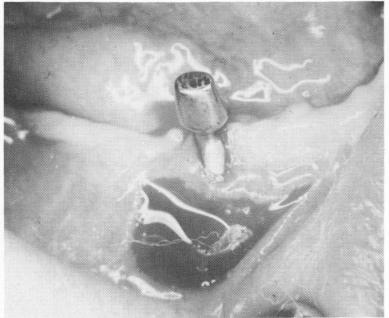

An accurate measurement of the soft tissue over-lying the four areas where the abutment posts will protrude should also be taken and sent to the technician. In this manner the height of the necks can be accurately determined. The tissue in the mandible is usually no thicker than 1 to 2 mm. However, if the tissue is not measured accurately and the neck is too long, the prosthesis-bearing post may be made much too short to firmly hold the superstructure. As an example, in one case it was necessary to cast a gold coping to cover the extra long neck so that the foreshortened abutment post could gain retention (Fig. 12-19). Unnecessarily long necks may also cause tension that results in the exposure of the primary strut (Fig. 12-20) . Such a situation may be

Fig. 12-20. The tissue sometimes recedes around an excessively long neck, especially if a high muscle attachment exists in the area. A relief incision is often made horizontally below the exposed strut and allowed to heal by secondary intention. This reduces the muscle pull, and sometimes the tissue readapts to its original height around the neck.

2 Tissue sometimes recedes around excessively long neck of dental implant